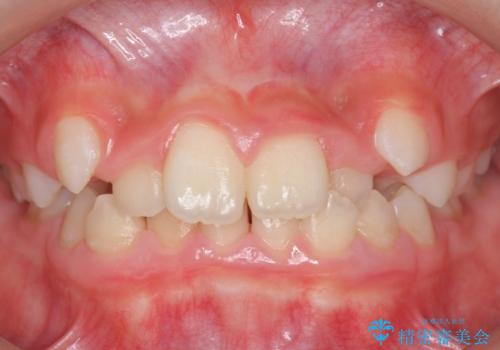

[ 前歯のねじれ・がたつき ] マウスピース矯正

![[ 前歯のねじれ・がたつき ] マウスピース矯正の症例 治療前](https://seimitsushinbi.jp/wp/wp-content/uploads/2024/02/4007c6479f6bce11863dcdd32ed5e39b-500x350.jpg?v=1708502552)